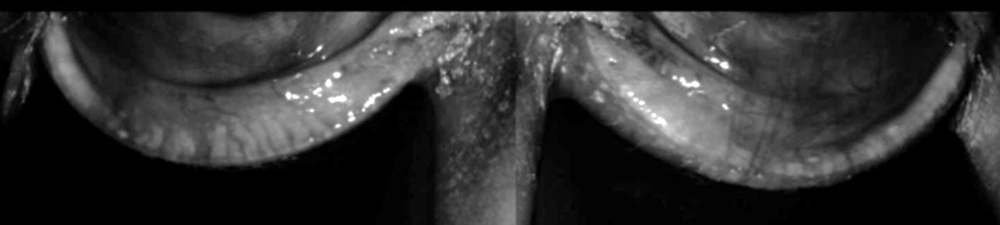

The best option would be to never use preservatives, but itโs not always feasible, so Dr. Galor tries to identify the patients who have toxicity from preservatives, mostly based on epithelial staining patterns, and tries to switch those that show adverse effects.

Dr. Galor offered several key principles in these scenarios: 1) Donโt have patients on medications they donโt need; carefully consider if they need chronic medications; 2) talk to patients about different types of medications, what theyโre buying over the counter, etc., and make sure theyโre making good decisions; 3) monitor for toxicity in anyone who uses chronic eye drops with preservatives; in the office, stain with vital dyes, and if you see it, thatโs a patient population where you can consider other options. It doesnโt have to be non-preserved drops; it could be options like SLT.

Stephen Pflugfelder, MD, also shared the concern of corneal and conjunctival epithelial toxicity with preservatives. This is most relevant to drops preserved with benzalkonium chloride (BAK), he said, which can cause corneal barrier disruption leading to an irregular and dry corneal surface that can reduce visual function and cause irritation. It can also cause death of conjunctival goblet cells, thus reducing secretion of tear-stabilizing mucin from these cells. Dr. Pflugfelder said that if possible, reducing the frequency of instillation or switching to a preservative-free formulation should be considered to help with the effects of these products. The risk of toxicity is related to the frequency of use and the BAK concentration. Usually, most patients can tolerate one drop with BAK preservative per day.